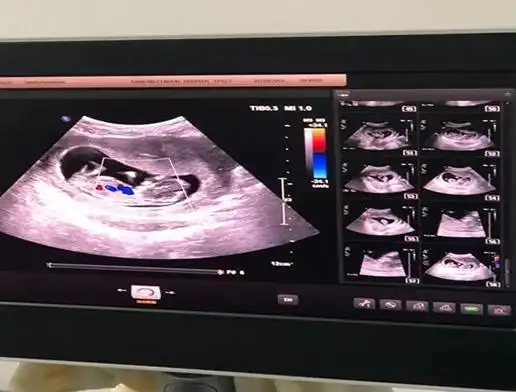

nt图弯着就是男孩,平是女孩nt躺着的女孩居多-爱子网

nt图有三条线是女孩怀孕12周nt图女孩的标志

nt一次过帮我看看是小男生还是小女生呀